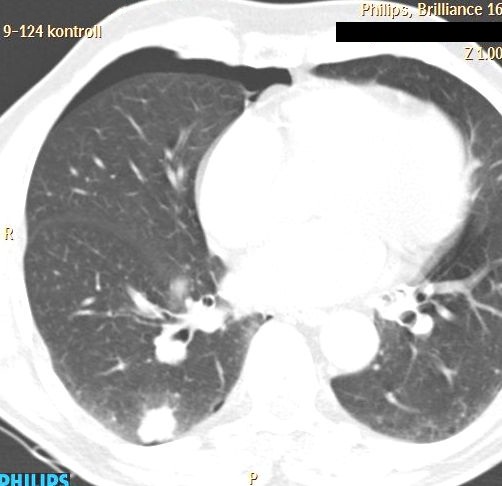

- Hemorrhage (subcapsular (figure 12.), parenchymal, intraabdominal (figure 13.), intrathoracic, pseudoaneurysm),

- Ptx (thoracic (figure 14.), mediastinal, infraclavicular, in case of subdiaphragmatic intervention),

A

Image

B

Figure 14. – PTX after lung biopsy (A: immediately after biopsy is only a small PTX, B: 5 minutes CT control)